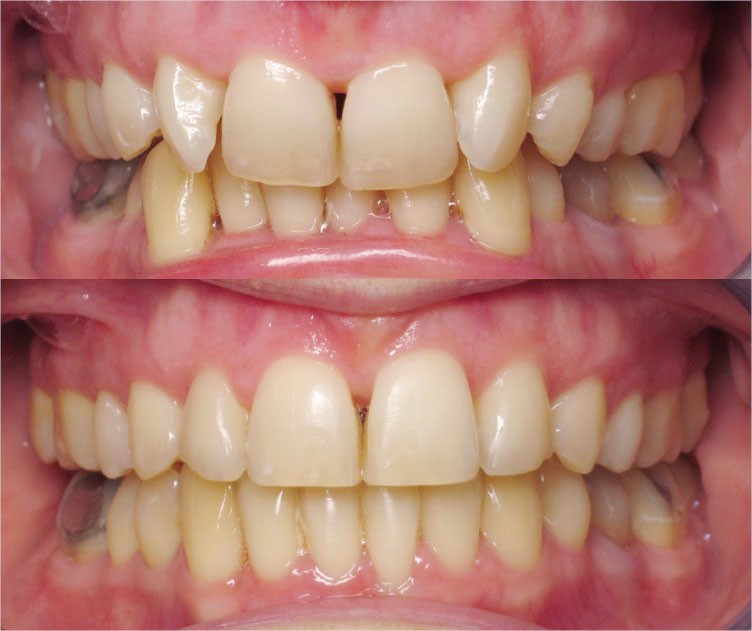

Nous lui avons donc proposé un traitement d’alignement avec maintien des 14 et 24 en position de 13 et 23 et optimisation du torque pour favoriser un développement des arcades et chercher à améliorer le sourire et le soutien labial.

L’objectif, en utilisant la technique Insignia est de réduire le temps de traitement de 28 à 18 mois avec 12 rendez-vous (fig. 5 à 14).

Les objectifs de traitement ont été remplis. Nous avons observé un excellent contrôle du torque et une absence de perte de l’occlusion postérieure grâce à la technique Insignia.